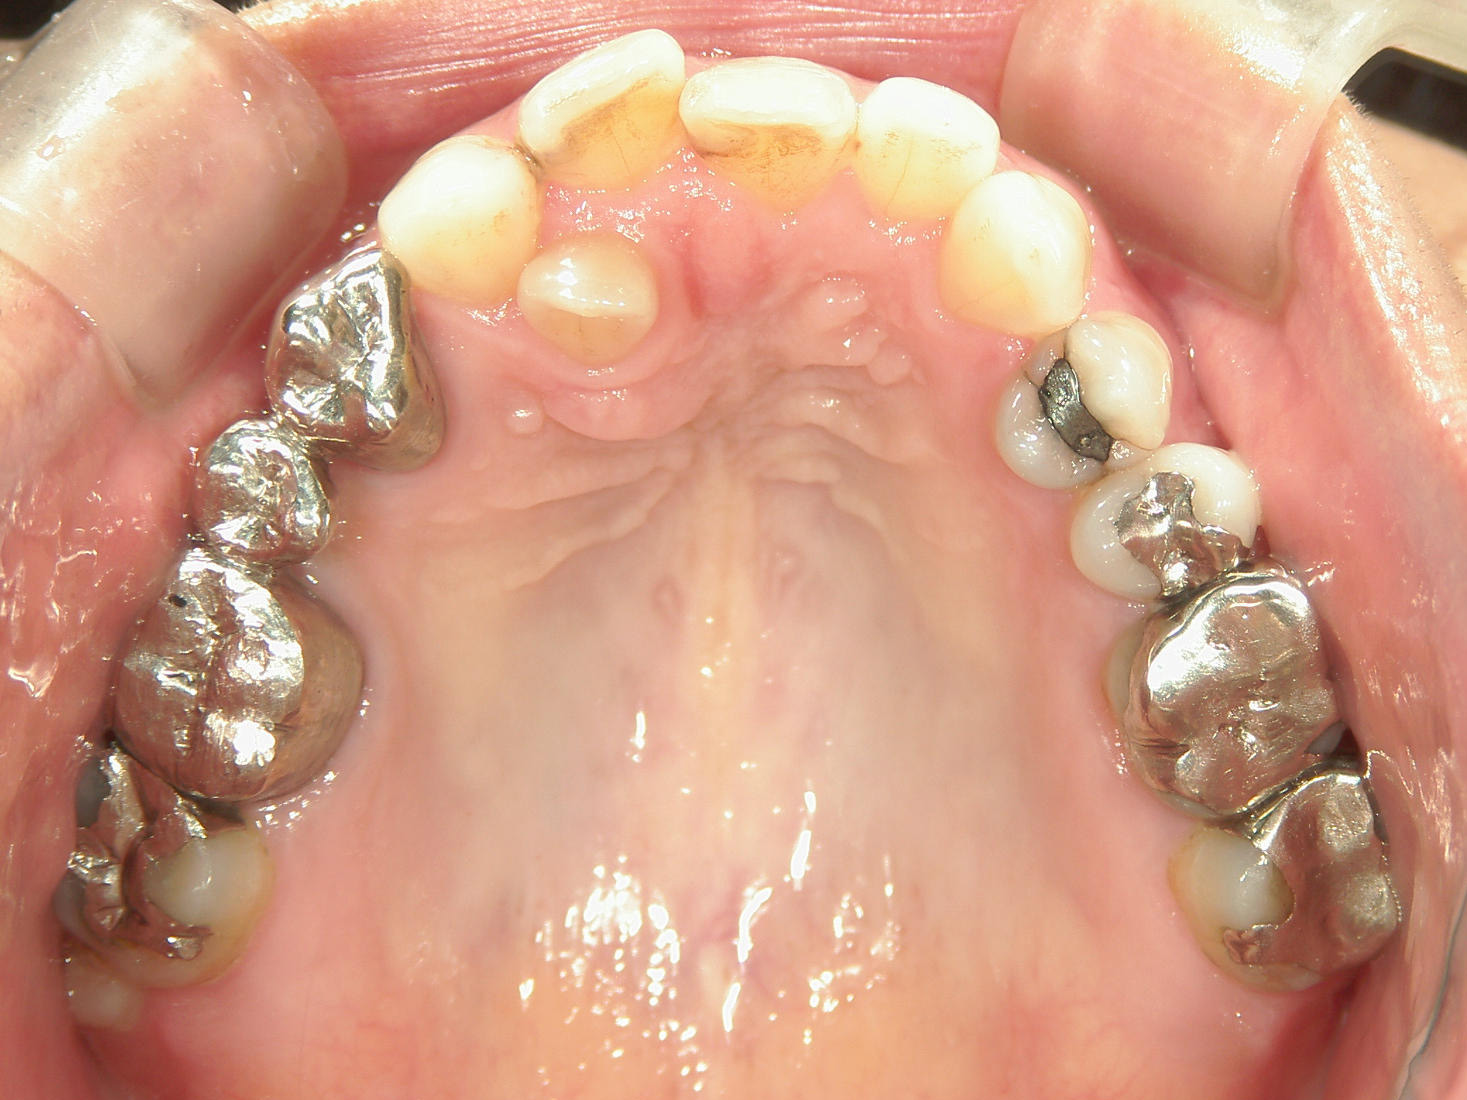

インビザライン矯正 症例(30)

主訴: 受け口、歯並びが気になる。

①患者様はインビザライン矯正をご希望でしたが、上顎骨が小さく、受け口になっているので、インビザライン矯正で治療するために「骨切断OPE」「矯正装置(MSE+フェイスマスク)」で上顎骨を拡大しました。